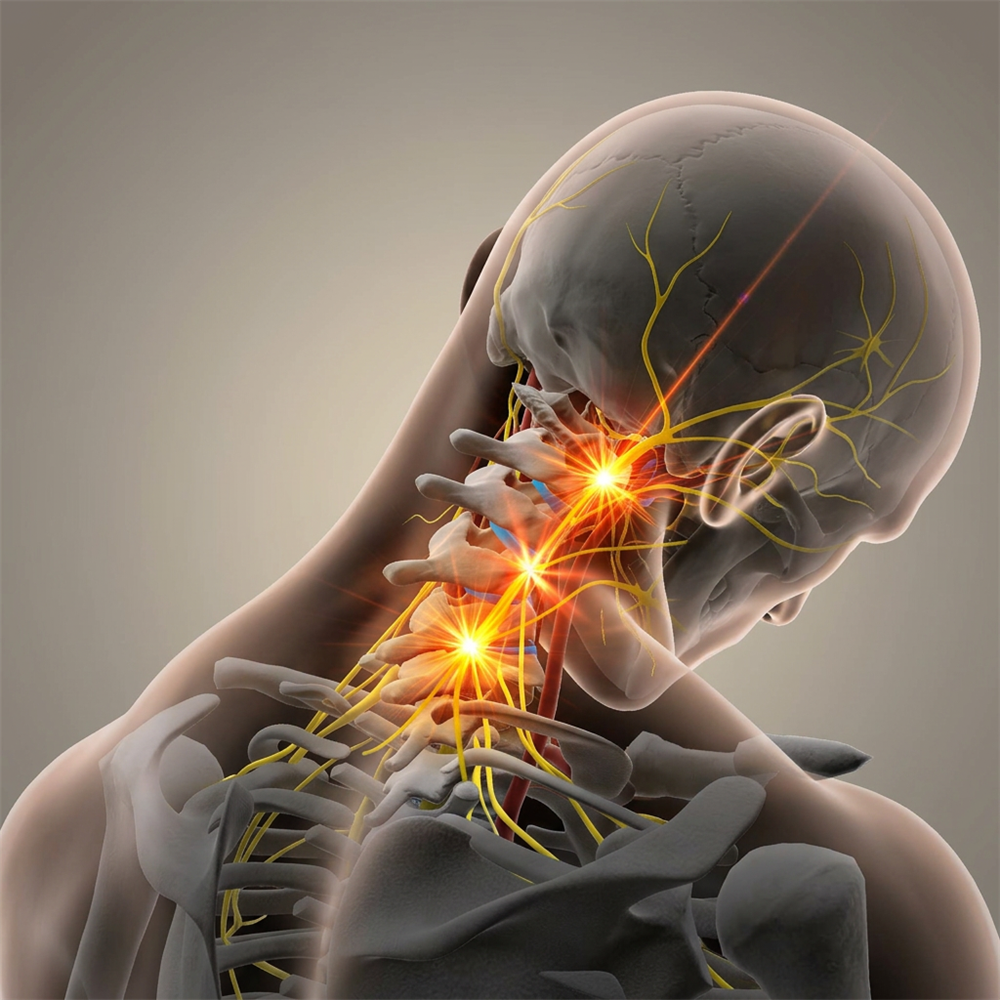

「頸源性頭暈」便是指疾病是與頸部問題最為相關。頸是連接頭部與軀幹的橋樑,它包含脊椎、血管 和神經組織(Fig.1),對活動和生存至關重要,任何傷害這條橋樑或這條橋樑出現病患,對維持人體健康或身體機能有關鍵影響,例如: 出現長期的頭暈頭痛。

(2)刺激交感神經:

抬頭或擺動頭部或頸椎,轉移體位刺激到交感神經,使頭暈、頭痛、眼花、心跳等症狀更加明顯。

(3)頸椎內外血管扭曲:

抬頭、擺動頭頸部或長期姿勢不良等,導致頸椎內外血管流動不暢順,影響血液來往腦區域,導致頭暈、頭痛。